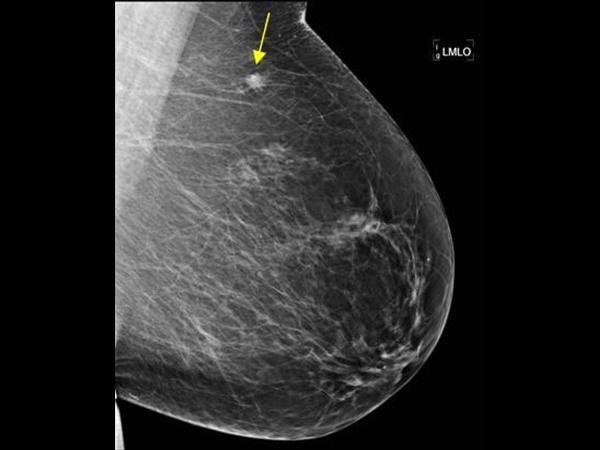

Ung thư vú

» Thông tin: Nữ giới – 71 tuổi.

» Lâm sàng: Khối tuyến vú.